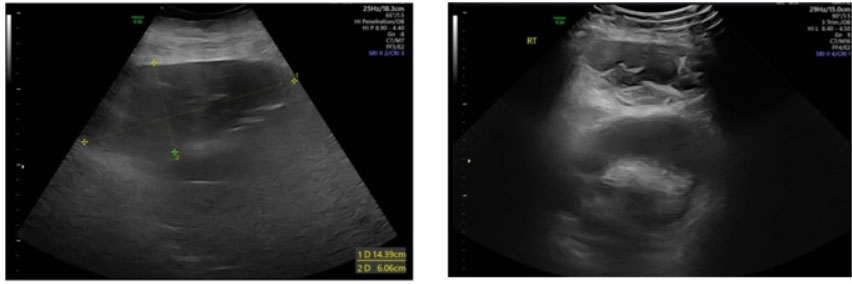

Figure 3: One month postoperative rectus sheath hematoma on US. Well-organized hematoma with smooth borders shows a significant color change compared to the surrounding tissue. A mixed cystic-solid state indicating the process of liquefaction and resolution.